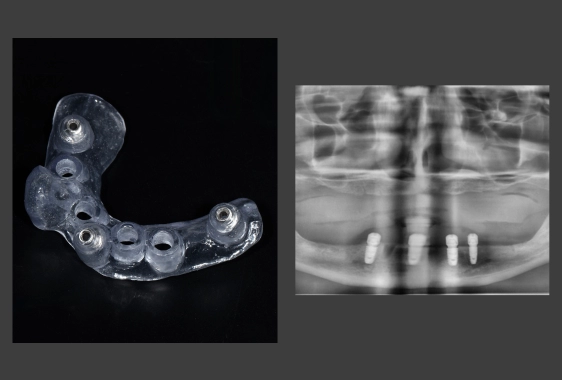

Хірургічний шаблон являє собою персоналізовану 3D-навігаційна капу з отворами для імплантів. Він виготовляється персонально під пацієнта та фіксується в ротовій порожнині протягом імплантації. Трафарет задає точний вектор, глибину, кут нахилу імпланту, забезпечуючи йому довгострокову стабільність і функціональність.

При імплантації без шаблону хірург орієнтується на клінічні маркери, форму альвеолярного гребеня, тактильні відчуття. За давньої втрати зубів анатомія щелепи змінюється, тому візуальні орієнтири стають нечіткими. Навігаційний шаблон мінімізує похибки та підвищує точність операції. Лікар вкручує імпланти в готові отвори, що гарантує точну відповідність попереднім розрахункам.

- Цифрове планування імплантації. Створюється віртуальна модель розміщення імплантів із точним розрахунком глибини, кута, позиції. Проводиться цифрова примірка майбутніх коронок – візуалізація майбутньої усмішки на екрані монітора.

- Моделювання виробу. Технік проєктує індивідуальний трафарет, доповнений направляючими отворами.

- 3D-друк. Принтер друкує пластиковий виріб по заданих параметрах.